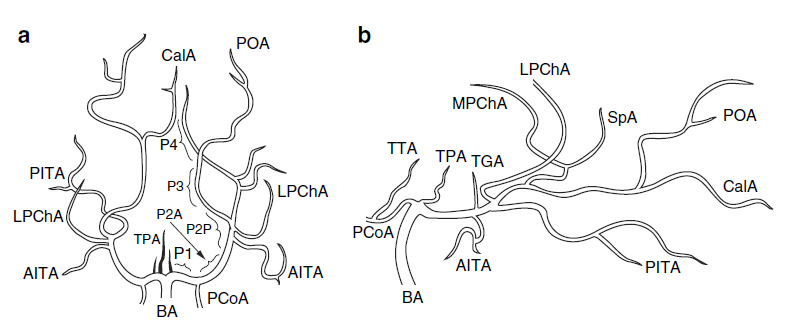

Posterior

circulation

Artery of Percheron – a variant

of the thalamoperforate arteries